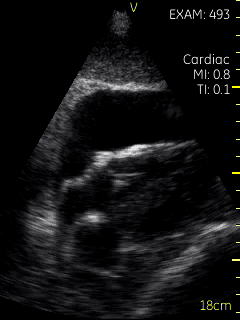

A 35-year-old male with a past medical history of end stage renal disease on hemodialysis and a chronic pericardial effusion secondary to dialysis presented to the Emergency Room (ER) with a 2-week history of a flu-like illness and pleuritic chest pain. He was compliant with dialysis three times per week. His blood pressure was 150/85 mmHg with a heart rate of 85 beats per minute and the remainder of his vital signs were stable. Pulsus paradoxus was not present. His jugular venous pulsation (JVP) was not visible, he had soft heart sounds, and no pericardial rub was heard. An ECG showed sinus rhythm with low voltages. Chest X-ray showed an enlarged cardiac silhouette. A point-of-care ultrasound (POCUS) exam using a hand-held GE V-scantm probe was used to look for a pericardial effusion. Two sets of subcostal images, performed 3 hours apart, are shown below (Figures 1 & 2; Videos S1-S4). The patient’s blood pressure and heart rate during the second set of images was 160/90 mmHg and 75 bpm respectively. A formal transthoracic echocardiogram conducted following the first set of POCUS images confirmed that there was a 3 cm circumferential pericardial effusion that had increased in size from a baseline of 1.5 cm. There was partial early systolic right atrial collapse but no other features of cardiac tamponade.

Video S1. Subcostal view of the heart showing partial right atrial collapse.

The case is of a 35-year-old male with acute pericarditis complicated by a large pericardial effusion with no evidence of tamponade clinically. The initial POCUS images show mild partial collapse of the right atrium with a small (< 2cm) and collapsing (> 50%) inferior vena cava (IVC) suggesting volume depletion.  The patient then received 500 cc of fluids during his scheduled dialysis session and a repeat POCUS scan 3 hours later shows near resolution of the right atrial collapse.

This case illustrates important aspects of cardiac tamponade physiology.  Given the stable blood pressure, the patient was not in clinical tamponade.  However, the POCUS images showed evidence of right atrial collapse, an early feature of the hemodynamic effect of increasing pericardial pressure.  This case illustrates that tamponade is a pathophysiologic continuum rather than an “all or none” phenomenon and the clinical manifestations of tamponade only occur in the latest stages of this continuum [1].  Cardiac tamponade is classically defined as compression of the heart by the accumulation of pericardial fluid under pressure [2]. When pericardial fluid accumulates slowly, pericardial compliance increases to accommodate the increase in volume, without an increase in pressure. As the pericardial fluid volume increases, the intrapericardial pressure increases.  With a further increase in pericardial fluid, the pericardium eventually becomes maximally stretched and can no longer expand to accommodate the additional pericardial volume [3].  The intrapericardial volume becomes fixed and the heart must compete with the intrapericardial fluid for this fixed volume. As the intrapericardial pressure increases, it first equalizes with the lower right sided chamber diastolic pressures, and then the left.  The result is decreased chamber size and diastolic filling, chamber collapse and a subsequent reduction in stroke volume. This results in falling of cardiac output and blood pressure which manifests as clinical cardiac tamponade. The right atrium is the first chamber to show signs of early compression, due to its thinner walls. Right atrial collapse is an extremely sensitive marker of cardiac tamponade, with a reported sensitivity of 100% and specificity of 82% in one study [4].

The physiologic findings of tamponade may occur earlier and at lower intra-pericardial pressures in hypovolemic patients. This phenomenon is known as “low pressure tamponade”. Clinical recognition of low pressure tamponade may be difficult because most patients lack the typical physical findings of pulsus paradoxus and distended neck veins. In the case of our patient, the small (< 2 cm) and collapsing (> 50%) inferior vena cava suggested a low right atrial pressure of approximately 3 mmHg.  Although a formal diagnosis requires a cardiac catheterization measuring intrapericardial and right atrial pressures, it is likely that our patient was in the very early stages of low-pressure tamponade that improved with the administration of fluids. Patients with low pressure tamponade may improve with fluids initially, but more severe cases often require aspiration of the effusion [5,6].